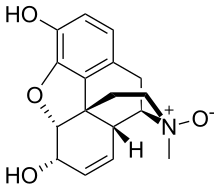

Active opiate metabolites

- Codeine-6-glucuronide

- Codeine-N-oxide (genocodeine)

- Heroin-7,8-oxide

- Morphine-6-glucuronide

- 3-Monoacetylmorphine

- 6-Monoacetylmorphine

- Morphine-N-oxide (genomorphine)

- Naltrexol

- Norcodeine

- Normorphine

Structures

| Active opiate metabolites | ||||

|---|---|---|---|---|

Codeine-N-oxide Codeine-N-oxide |

Heroin-7,8-oxide Heroin-7,8-oxide |

Morphine-6-glucuronide Morphine-6-glucuronide |

6-Monoacetylmorphine 6-Monoacetylmorphine | |

Morphine-N-oxide Morphine-N-oxide |

Naltrexol Naltrexol |

Norcodeine Norcodeine |

Normorphine Normorphine | |